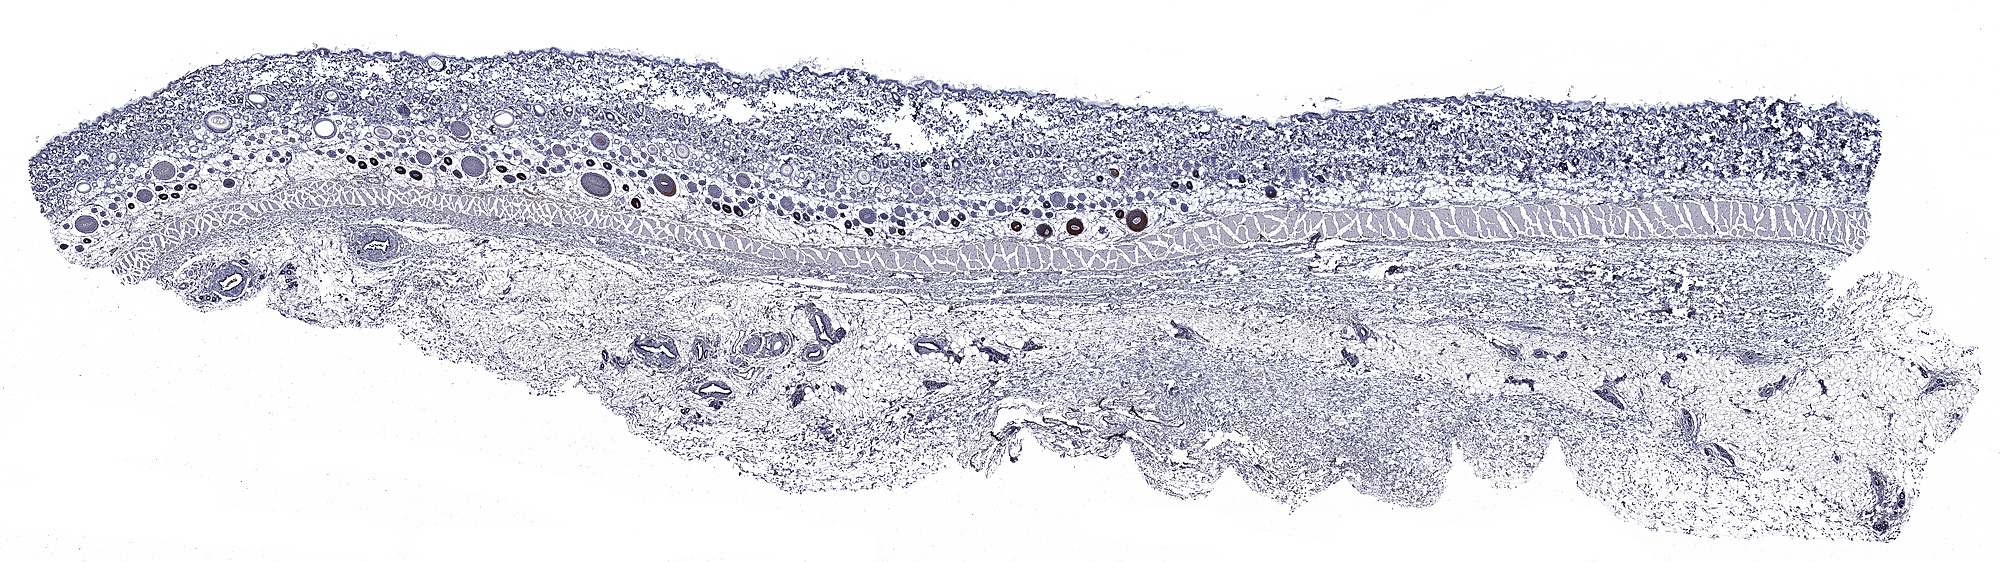

Metallothionein: Immunoperoxidase staining of formalin-fixed, paraffin-embedded rat skin showing cytoplasmic and nuclear in the hair follicles.